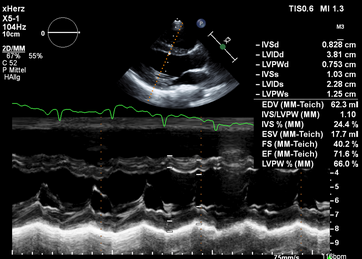

Die Ultraschalldiagnostik, in der Kardiologie Echokardiographie stellt neben dem EKG eine wichtige nicht-invasive Untersuchungsmethode bei der Abklärung von Herzerkrankungen dar. Die Echtzeitbilder des Herzultraschalls zeigen Veränderungen und Defekte des Herzmuskels, der Herzkammern, des Klappenapparates und der zu- und abfließenden Gefäße.

Durch die Echokardiographie lassen sich geschädigte Muskelabschnitte des Herzens nach einem Herzinfarkt, bei Menschen mit koronarer Herzkrankheit (KHK) oder eine Herzmuskelentzündung genauer bestimmen.

Zu den Standartverfahren zur Diagnostik von Herzerkrankungen gehört die transthorakale Echokardiographie (TTE). Dabei legt der Untersuchende den Ultraschallkopf auf definierte Areale der Brustwand und kann so Unregelmäßigkeiten sehen. Sie ist vergleichbar mit einem herkömmlichen Ultraschall. Zusätzliche Informationen ergeben sich durch die Hinzunahme von Doppler- und Farbdopplerdarstellungen. Durch das Messen der Strömungsgeschwindigkeit und das Nachweisen der Strömungsbeschleunigungen wird die Funktion/Dichtigkeit der Herzklappen kontrolliert.